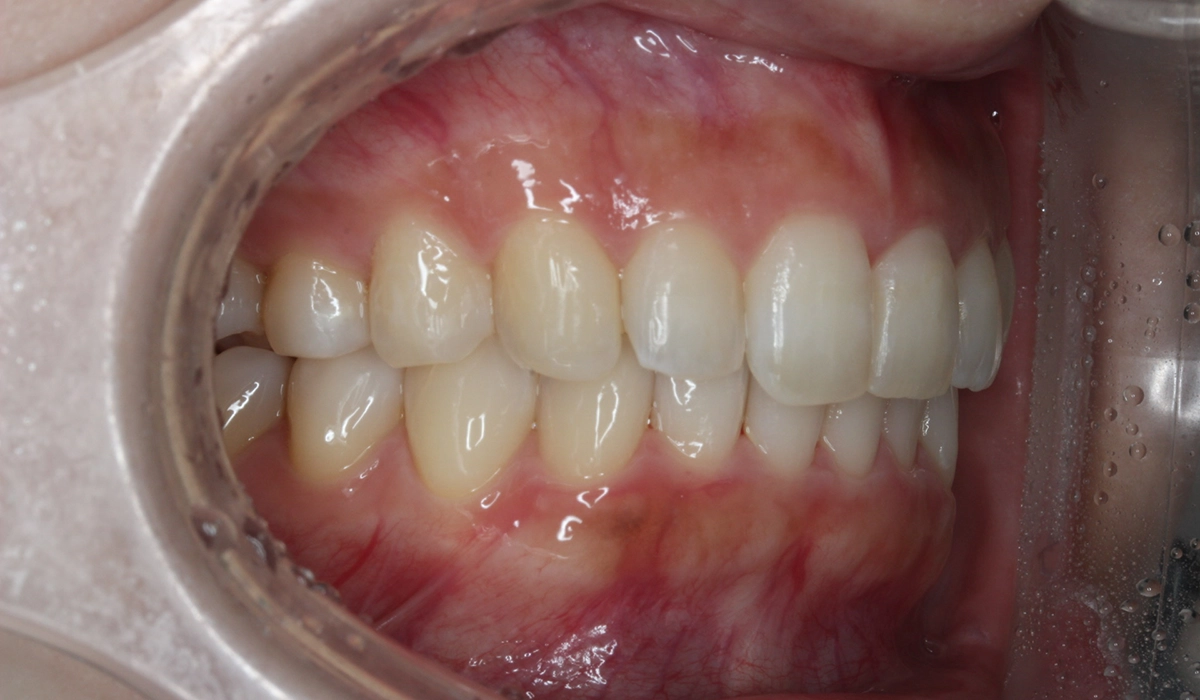

術後:左側

非抜歯と可能な限りIPRなしにこだわったため、大臼歯の遠心移動を主体としてスペースを確保したため治療期間がやや長くなるも18カ月で完了致しました。

| 治療期間 | 18カ月 |